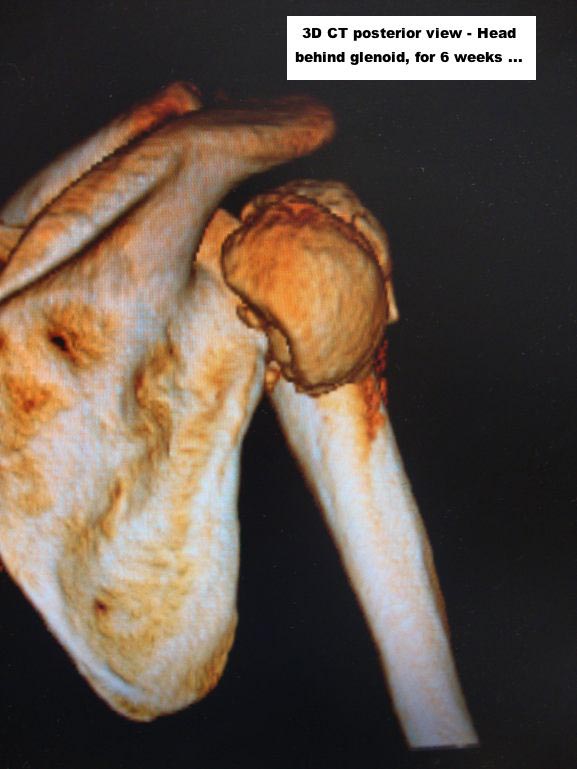

При переломах проксимального плеча, кроме обычных рентген снимков, необходимо сделать КТ исследование. Особенно 3D реконструкция, которая даст полную информацию о расположении фрагментов, потому что от количества фрагментов зависит тактика лечения. Переломы из 4х фрагментов приведет к остеонекрозу и поэтому прямое показание к эндопротезированию. Переломы с меньшим количеством фрагментов успешно могут быть синтезированы!

Из всех возможностей лечения протезирование было бы самым легким решением? и можно остановиться на hemiarthroplasty. Здесь костные фрагменты расположились разнонаправленно, и при решении на протезирование желательно сохранить большой бугорок.

I cannot actually recognize, very much as I suppose you cannot either, which was the initial injury pattern and thus its classification. Either both tuberosities did not split apart as it sometimes happens or they have united afterwards.

Maybe a CT / MRI would afford more information about the actual fragments morphology and even perfusion in order to consider a reconstruction with or without an osteotomy between both tuberosities. It’s quite difficult believing in a full reconstruction due to the limited size and situation of the head, but one never knows, … mainly if you are a specially gifted surgeon and you’ve got a full bag of lucky vibrations.

Here are some photos, of chronic, locked, 4 part posterior dislocation, 2 months old, that I did September/2011. Patient is 67, very, very active - had a really reasonable, honest clinical result ...